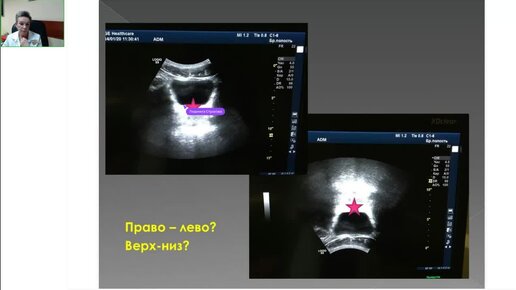

Погрузитесь в мир ультразвуковой диагностики с записью семинара "Пропедевтика ультразвуковой диагностики". Доступно о сложном